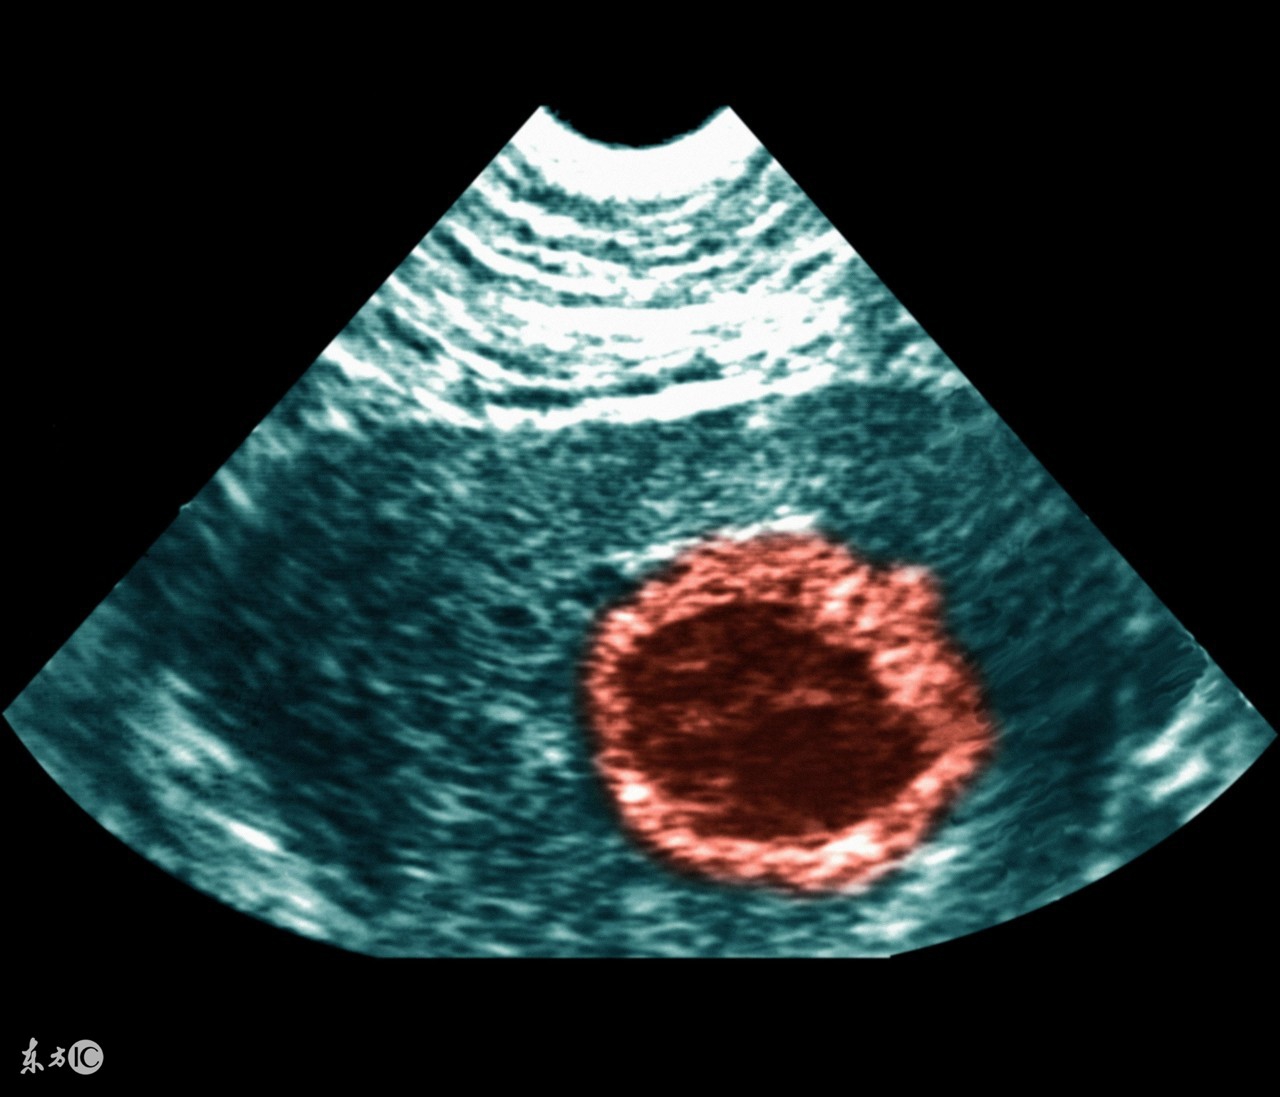

怀孕后,孕妈妈就盼着能顺利度过孕早期;经常听到谁谁谁流产,听多了让人很担心。现在医学技术的发达,如果出现什么问题,及时就医也可以避免不幸发生。但是,当孕妈妈遭遇先兆流产时,到底要不要选择保胎?听听妈妈们有什么经验之谈......

但是,确实存在优胜劣汰,也不能过分保胎。在怀孕早期有出血情况可以先这么做:

马上到医院检查、针对性保胎